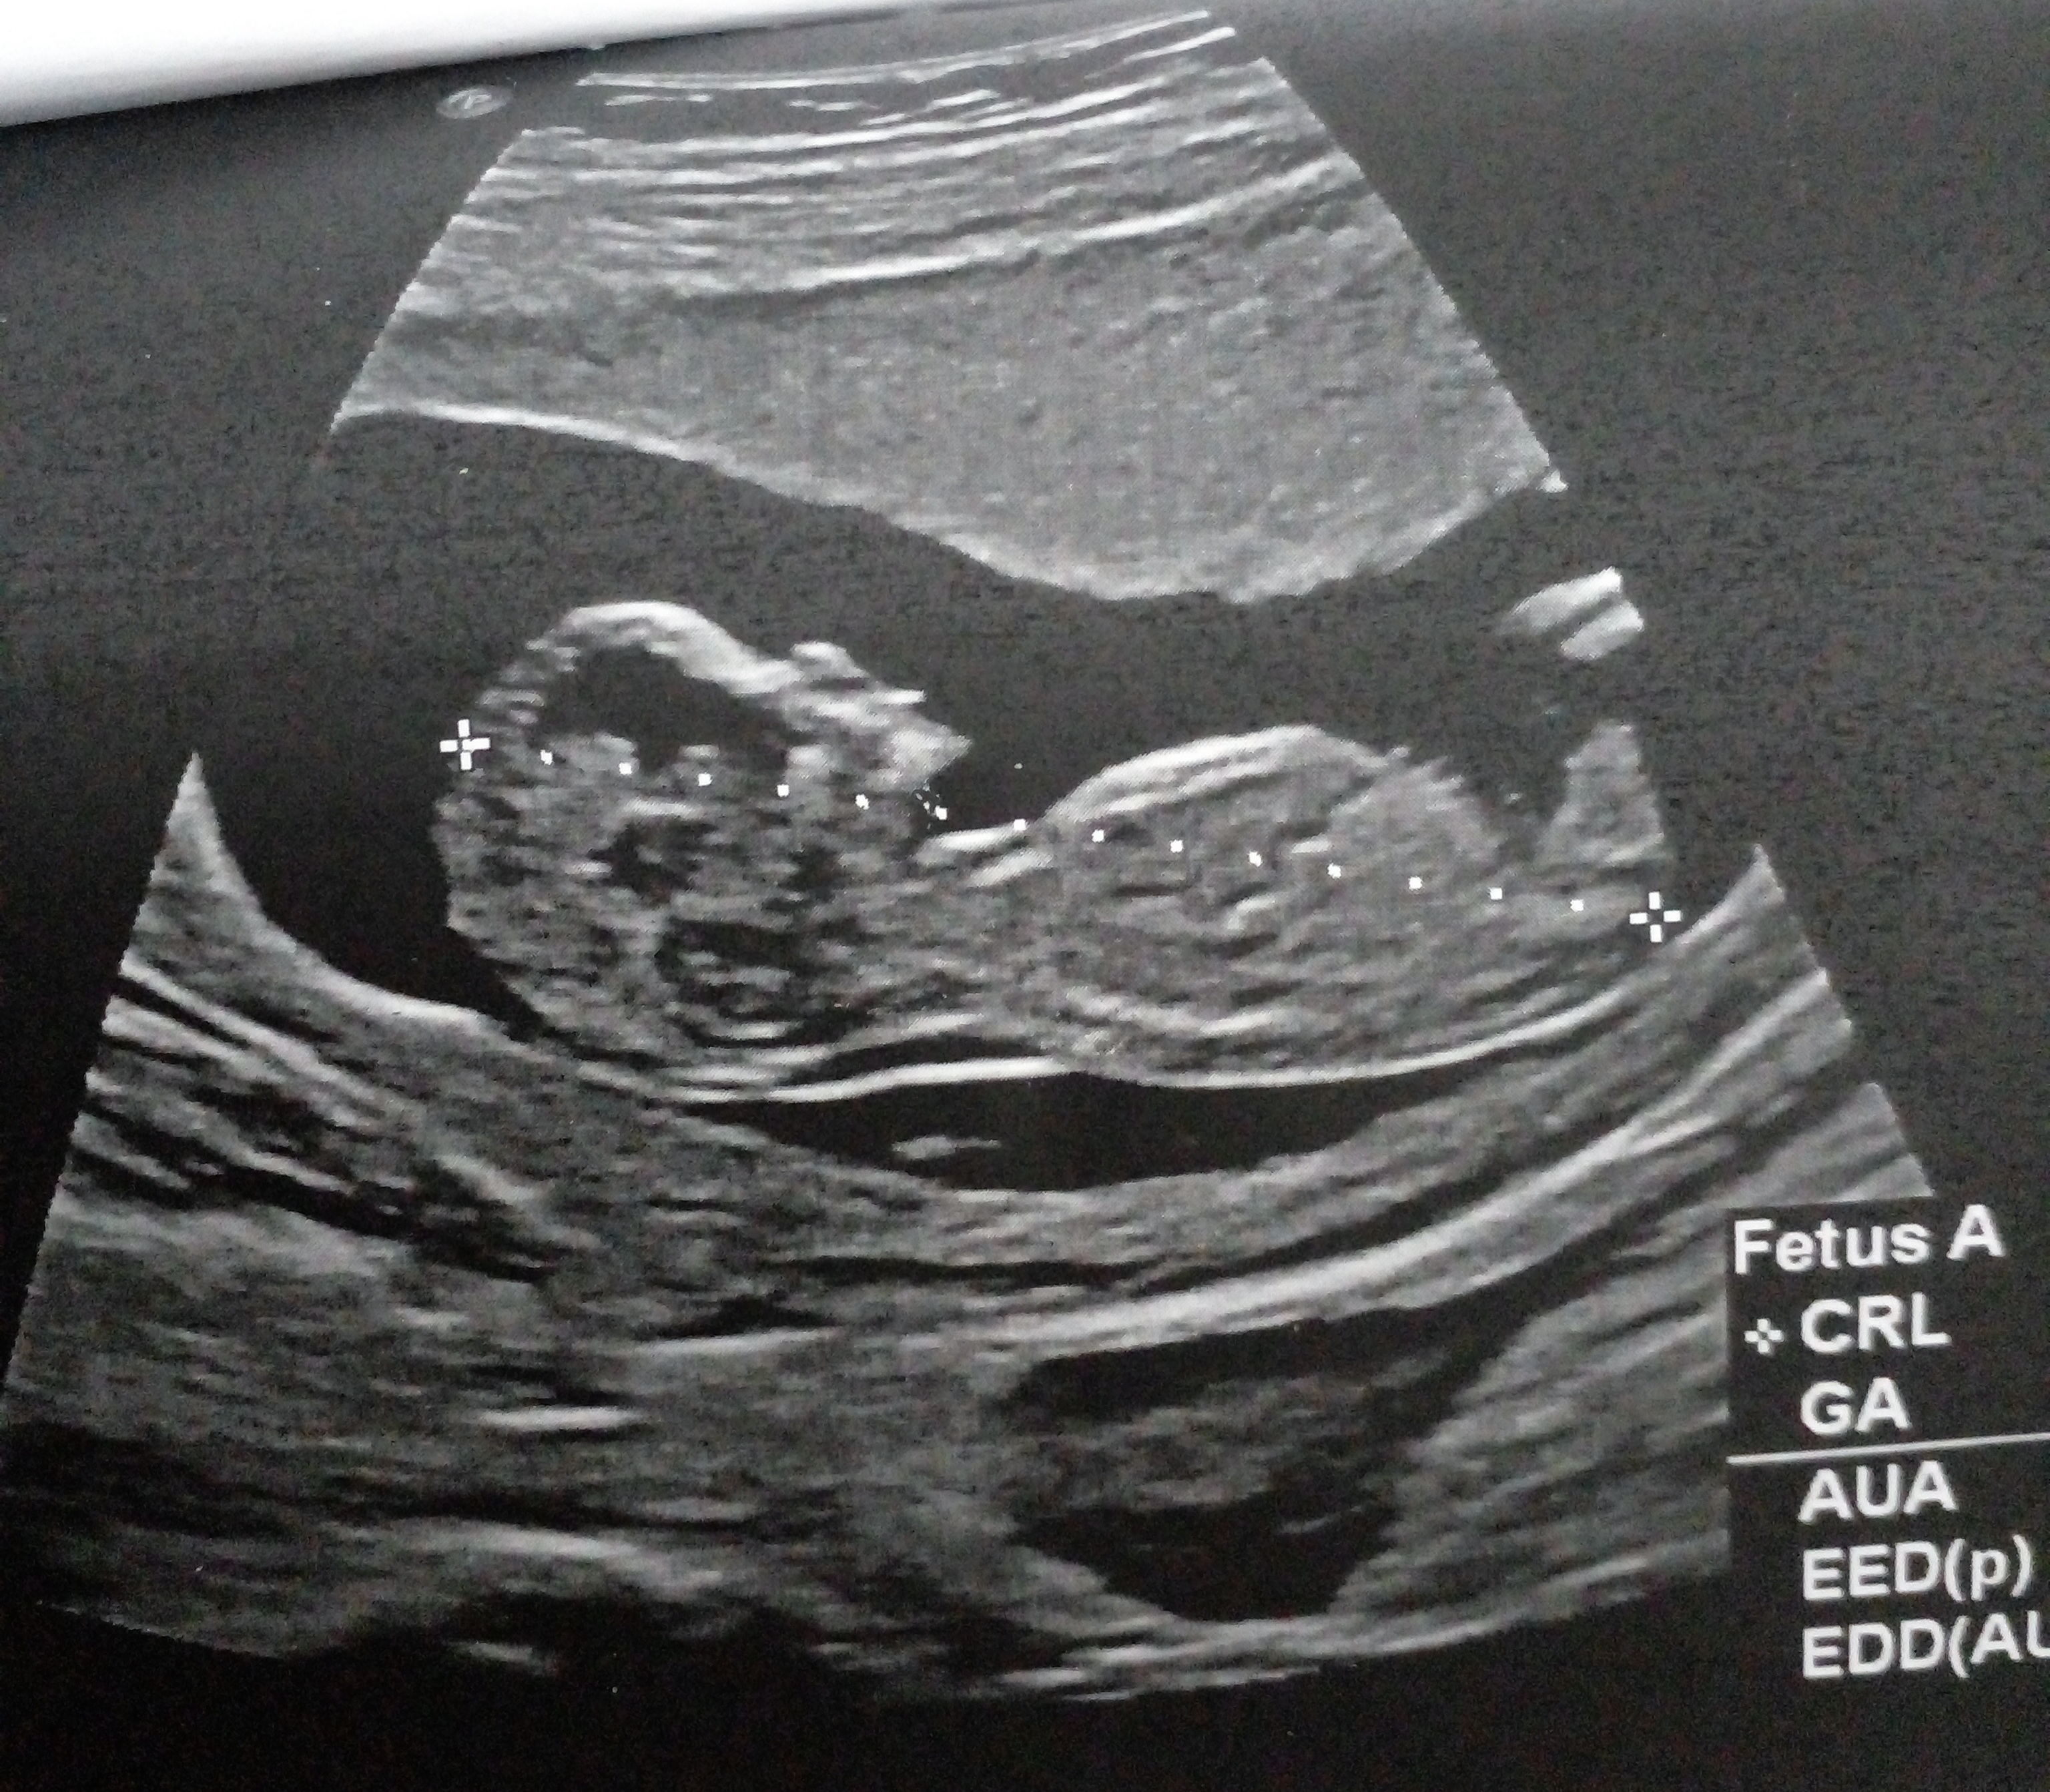

اخی عزیززززم بسلامتی. من میگم یه پسر یه دختر. اسی علایمت چی میخام بدونم دوقلو داشتی علایم بارداریت چیا بود قبل اینکه بری سونو بفهمی دوقلوه.

عزیزم انشاله خدا بهترین ها رو نصیبت کنه ، فقط بتای بالای داشتم بقیه علایم مشابه بقیه بود

ممنون عزیزم واقعا از روی عکس مشخصه یا حدس میزنید ؟ انشاله بهترین ها قسمت خودتون بشه

ن معلومه عزیزم 🤍

والا تا جایی ک تجربه دارم باید همین باشه ی گل پسر ی شاهزاده خانوم

حالا 18 هفته ک رفتی آنومالی تگم کن ببینم درست گفتم😄😄😄